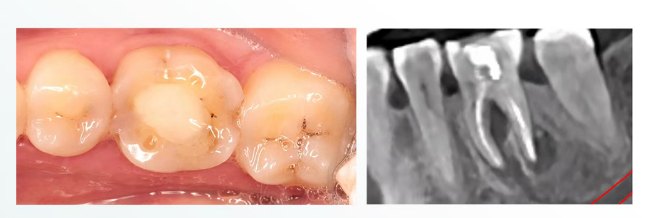

患者性别:女 年龄:33岁

主诉:左下后牙反复隐隐不适一年

现病史:患者自诉左下后牙外院根管治疗两次,近一年来隐隐不适,

不敢咬合,遂至我院就诊。

既往史:外院看牙史,既往体健。

检查:颌面可见外院牙色充填物,颊侧黏膜可见一瘘管,

无松动,叩 (+) ,冷测:无反应,余无异常; CBCT片示:根尖可见大面积低密度暗影。

说明:怀疑失败原因--未行冠修复,导致微渗漏,预备

宽度不足,未能完全清创,化学预备不够,疑似侧枝根管清理不到位,不排除隐裂可能性。